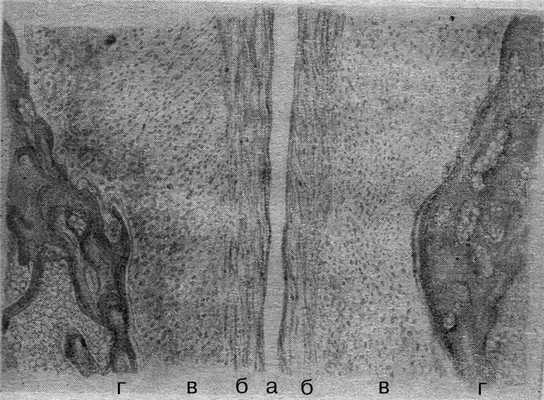

Одно из наиболее детальных описаний морфологии ЛС приведено М.Ф. Айзенбергом (1962). По его данным, ЛС «обладает половыми особенностями и имеет индивидуальные различия. Наблюдаются все виды соединений - от синхондроза до настоящего сустава. У детей и лиц мужского пола ЛС представлено чаще в виде бессуставного сращения - симфиза. Появление же щели в центре фиброзного хряща, делающей его несколько подвижным, превращает это соединение в так называемый полусустав. В тех случаях, когда щель проходит через всю высоту и толщину фиброзного хряща и смыкается с периферическими связками, соединение становится подвижным. Особенности строения и состояния лонного сочленения у женщин, безусловно, находятся в тесной связи с эндокринными и функциональными процессами, происходящими в организме». По данным М.Ф. Айзенберга (1962), морфологически хрящевая межлобковая пластинка неоднородна: большая ее часть представлена гиалиновым хрящом, по периферии от межлобковой щели расположена зона фиброзного хряща. С возрастом гиалиновый хрящ вытесняется и в ряде случаев определяется в виде отдельных островков (рис. 2). Рисунок 2. Морфология лонного сочленения у пациентки фертильного возраста (по М.Ф. Айзенбергу). а - щель лонного сочленения; б - фиброзный хрящ; в - гиалиновый хрящ; г - кость.

Одно из наиболее детальных описаний морфологии и структуры ЛС приведено в 1962 г. По его данным, ЛС «обладает половыми особенностями и имеет индивидуальные различия. Наблюдаются все виды соединений — от синхондроза до настоящего сустава. Особенности строения и состояния ЛС… у женщин… безусловно… находятся в тесной связи с эндокринными и функциональными процессами, происходящими в организме». Морфологически хрящевая межлобковая пластинка неоднородна — большая часть ее представлена гиалиновым хрящом, по периферии от межлобковой щели расположена зона фиброзного хряща. С возрастом гиалиновый хрящ вытесняется и в ряде случаев определяется в виде отдельных островков [8].